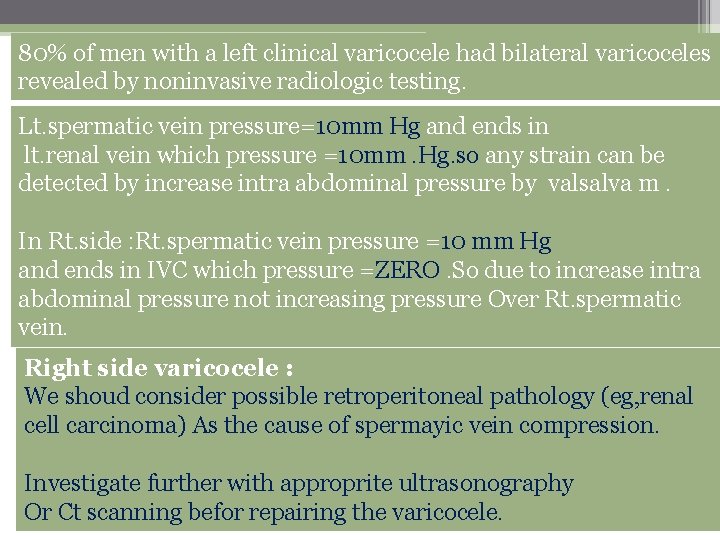

Etiology Varicoceles are much more common (approximately 80 -90%) in the left testicle than in the right because of several anatomic factors, including: 1) the angle at which the left testicular vein enters the left renal vein. 2) the lack of effective antireflux valves at the juncture of the testicular vein and renal vein. 3) the increased renal vein pressure due to its compression between the superior mesenteric artery and the aorta( the nutcracker phenomenon) 4) Increased length of the left testicular vein: The left vein is 8 -10 cm longer than the right testicular vein

80% of men with a left clinical varicocele had bilateral varicoceles revealed by noninvasive radiologic testing. Lt. spermatic vein pressure=10 mm Hg and ends in lt. renal vein which pressure =10 mm. Hg. so any strain can be detected by increase intra abdominal pressure by valsalva m. In Rt. side : Rt. spermatic vein pressure =10 mm Hg and ends in IVC which pressure =ZERO. So due to increase intra abdominal pressure not increasing pressure Over Rt. spermatic vein. Right side varicocele : We shoud consider possible retroperitoneal pathology (eg, renal cell carcinoma) As the cause of spermayic vein compression. Investigate further with approprite ultrasonography Or Ct scanning befor repairing the varicocele.